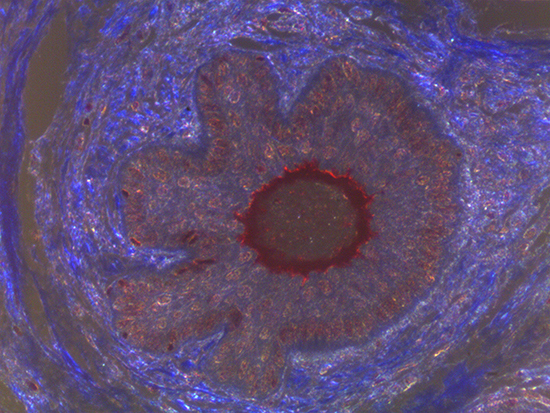

Figure 1: Brightfield Image of Dermal Tissue

Figure 2: Darkfield Imaging of Dermal Tissue

When comparing Figures 1 and 2, the visual differences are significant. A brightfield image is formed with the illumination source below the sample, and then transmitted light propagates through the sample to the sensor forming a bright, white background with sharp color. A darkfield image is formed by directing light at an oblique angle through the sample, forming a hollow cone of light which is collected by the objective. Darkfield illumination typically yields a dark background with sharp color, but in the case of Figure 2, the collagen and muscle fibers interfered with the light path and caused a blur of light and color. The dark background is hardly evident and only two distinct colors are visible. When analyzing histological stains, brightfield illumination is the preferred technique for lighting a sample.

Figure 3: Brightfield Image of Dermal Tissue filtered with Green

Figure 4: Brightfield Image of Dermal Tissue filtered with Red

When comparing Figure 3 with Figure 4, there is once again a significant visual difference. The most obvious feature is the change in color from green to red due to a different hardcoated filter being positioned in the optical path. The less obvious difference is the varying contrast levels caused by the filters at specific regions of the dermal tissue. For example, Figure 3 exhibits a distinct ring at the central region of the cell with additional matter within. In Figure 4, the ring is extremely faint and the internal matter is not visible. With that said, the cell and surrounding dense materials are more evident in Figure 3, whereas the muscle fibers and collagen are more pronounced in Figure 4.